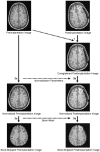

Fig 1.

The image data processing is fully automated and consists of the following steps: 1) coregistration of the postimplantation image to the preimplantation image; 2A) normalization of the preimplantation image; 2B) normalization of the postimplantation image based on the transformation parameters derived from the normalization of the preimplantation image; 3A) brain extraction in the preimplantation image; and 3B) brain extraction in the coregistered postimplantation image by using the skull-stripped preimplantation image as a mask.